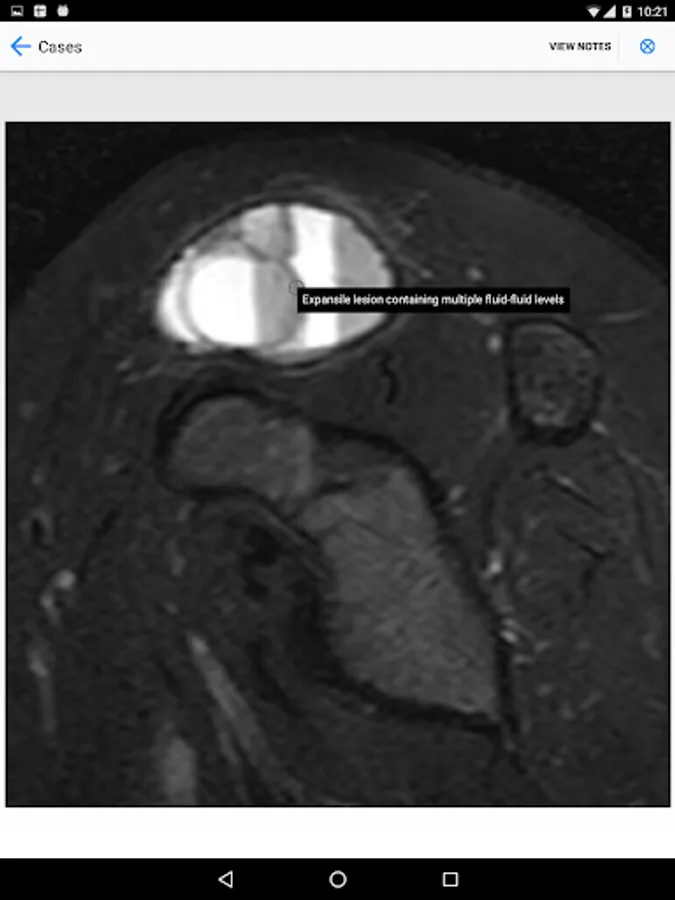

BoSTT brings the user a real experience of frequent and rare, typical and more unusual cases of bone and soft tissue tumours. Each case has a clinical history, high resolution radiology and pathology images, diagnosis, treatment and learning points.